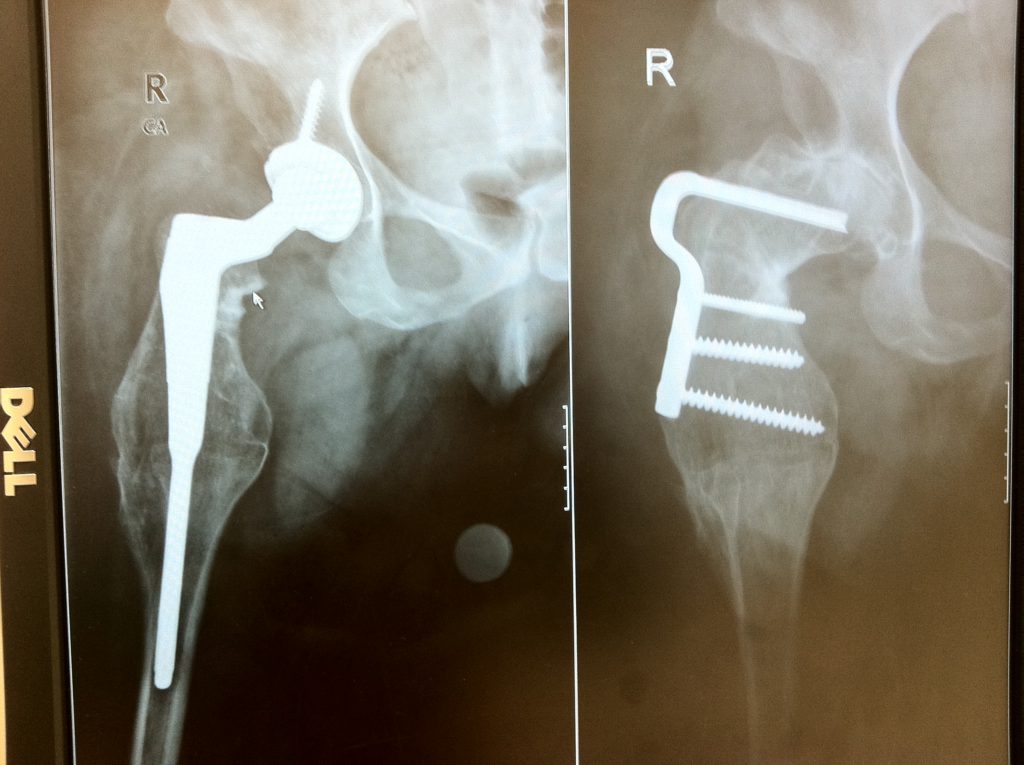

Patient image of: Katherine Ventres

Doctor Mathias Bostrom and HSS changed my life. I was born with PFFD a rare birth defect where I was missing my femur bone. I went to see Doctor Bostrom due to horrible hip pain. I had searched high and low for a specialist in CT but to no avail. After months of research and doctors visits I found myself reading the profiles of orthopedic surgeons at Hospital for Special Surgery. After reading Dr Bostrom's profile I knew he was the surgeon I had been looking for. He and his team built me and one of a kind hip replacement and seven months later, in September of 2010, I was in surgery. That will be 7 years ago this September. I saw him today and am so incredibly pleased that the procedure has been a huge success. Doctor Bostrom is a life changing surgeon. I am so grateful for his knowledge and expertise.